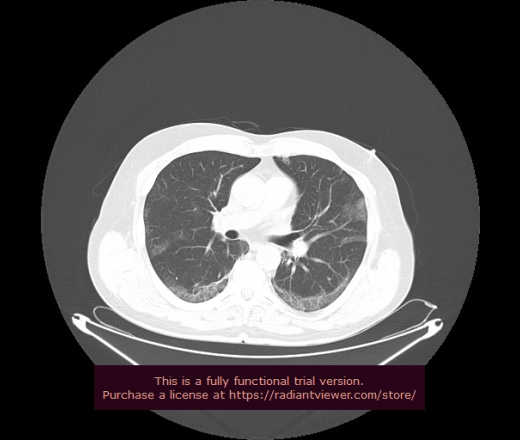

Уважаемые коллеги, если имеется интерес, сможете ли Вы спрогнозировать дальнейшее +-одинаковое течение процесса у 4 данных разных пациентов? Зацепиться где-то можно очень просто, где-то нельзя.